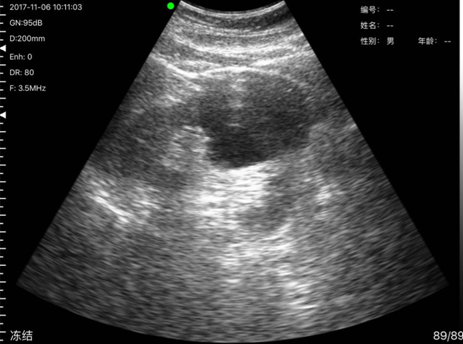

病例7,姓名:罗x姬,性别:女,年龄69岁,发现其胆囊有两亮点疑似胆囊结石,后经上级医院复查确诊为胆囊结石。

胆囊结石与上级医院复诊结果一致

胆囊结石